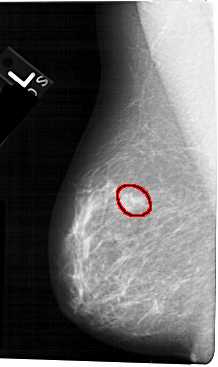

FILE: A_1323_1.LEFT_CC.OVERLAY

TOTAL_ABNORMALITIES 1

ABNORMALITY 1

LESION_TYPE MASS SHAPE OVAL MARGINS OBSCURED-ILL_DEFINED

ASSESSMENT 4

SUBTLETY 2

PATHOLOGY BENIGN

TOTAL_OUTLINES 1

BOUNDARY